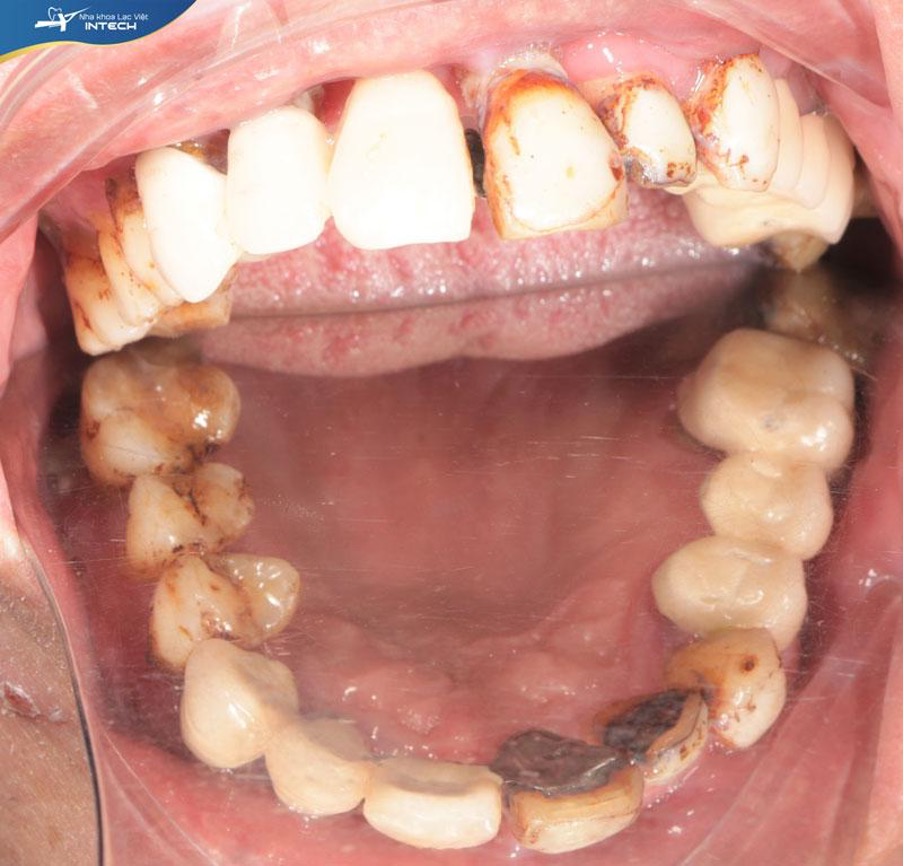

Khách hàng Nguyễn Duy Khích (Phú Thọ) đến với Nha khoa Lạc Việt Intech trong tình trạng mất nhiều răng hàm, các răng còn lại bị xô lệch, lung lay. Bên cạnh đó, trong miệng của chú còn xuất hiện các ổ viêm nha chu gây đau nhức, ảnh hưởng tới khả năng ăn nhai.

Tình trạng răng trước đây của chú Khích

Sau khi thăm khám và chụp phim, bác sĩ Nguyễn Hoàng Dương - Chuyên gia cấy ghép và phục hình răng Implant tại Nha khoa Lạc Việt Intech nhận định tình trạng trước của chú Khích:

• Mất nhiều răng hàm dưới

• Lung lay toàn bộ răng 2 hàm

• Viêm nha chu nặng, nhiều mảng bám cao răng

• Xuất hiện các ổ viêm nha chu trải dài trong miệng ở cả hàm trên và hàm dưới

Chú Khích đã làm cầu sứ nhóm răng cửa và răng hàm ở hàm trên

Bác sĩ Dương chia sẻ: “Nguyên nhân dẫn đến tình trạng này một phần đó là do việc chú Khích đã làm cầu răng sứ trước đây. Phương pháp làm cầu răng sứ lâu ngày gây đọng dắt thức ăn và dẫn đến tình trạng viêm chân răng. Ngoài ra, tình trạng mất một vài chiếc răng không được xử lý luôn khiến cho các răng xung quanh bị xô lệch. Khớp cắn không được chia sẻ lực nhai đồng đều làm cho các răng còn lại trên miệng bị lung lay theo thời gian và rụng dần. Tình trạng răng cửa hàm trên bị lung lay, không có phương pháp xử lý và điều trị sẽ có xu hướng đẩy chìa ra phía ngoài gây mất thẩm mỹ.”